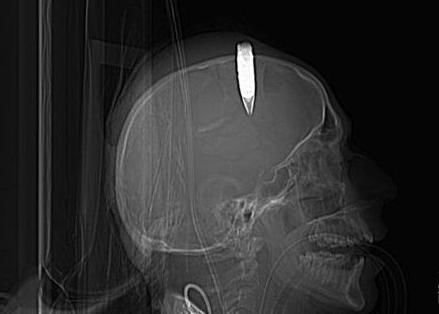

一名士兵的頭部嵌入子彈的X光片(資料圖)

國際在線訊 據(jù)《世界報》12月29日報道,俄羅斯一名退休工程師被認為是個醫(yī)學(xué)上的奇跡。他82年前頭部遭槍擊,子彈留在了腦袋里,但他安然無恙,生活也沒受到任何影響。

《新英格蘭醫(yī)學(xué)期刊》報道稱,在該男子3歲時,他的哥哥玩耍時不小心開槍擊中了他的頭部。隨后,他暈厥了長達數(shù)小時,但后來沒經(jīng)過任何治療就痊愈了。長大后,該男子還成為了出色的工程師。

這顆嵌在他腦袋里的子彈幾乎將陪伴這名85歲的男子一生,但他的健康卻幾乎沒受到任何影響。